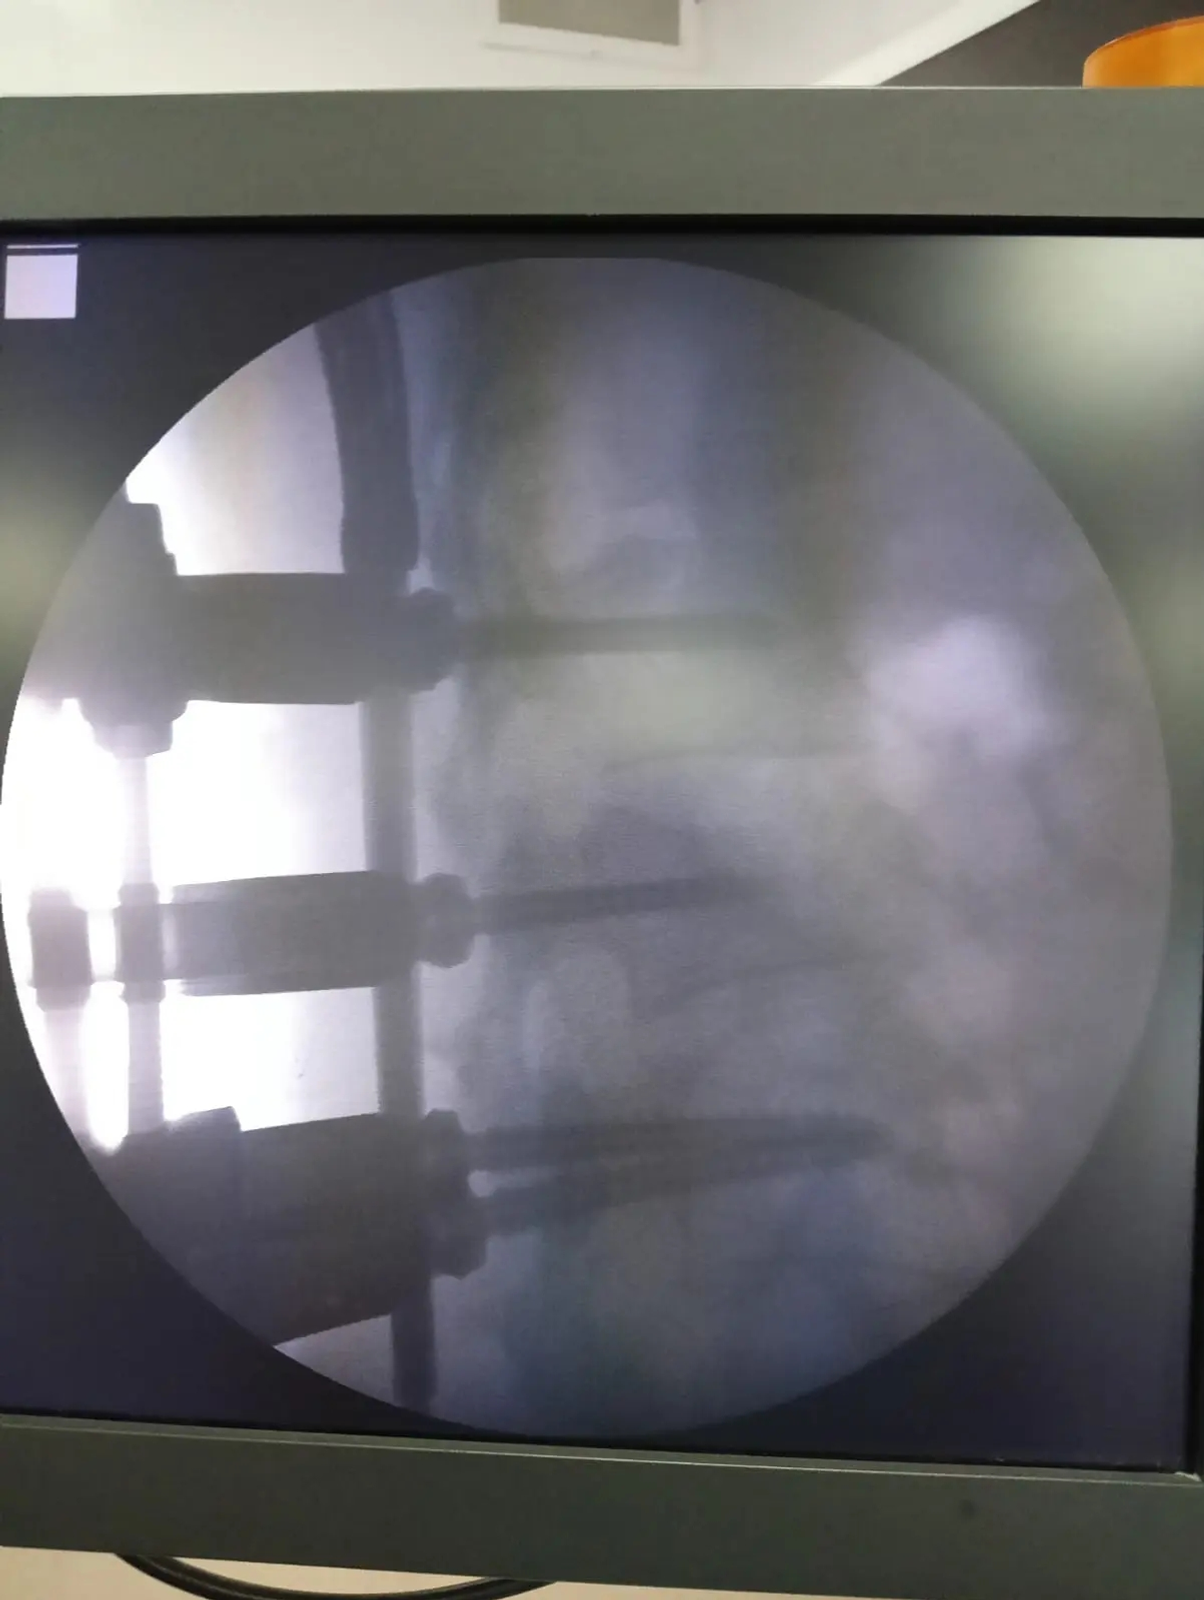

Табиблар ике сантиметр озынлыкта гына кечкенә кисемнәр ясап, махсус кораллар ярдәмендә умыртка баганасын торгызырга ярдәм итәчәк конструкцияләр — винтлар һәм штангаларны урнаштырган.

Хирургик тыкшыну барышында умыртка сөяге дөрес формага кайтарылган, умыртка баганасының зарарланган өлеше ышанычлы итеп беркетелгән. Шулай ук винт ярдәмендә сөяк кисәге тоташтырылган. Бу аңа дөрес итеп ялганырга ярдәм итәчәк.

Операцияне нейрохирург Сергей Цыглеев башкарган. Аңа операция шәфкать туташлары Наталия Ильяхунова һәм Римма Шакирова ярдәм иткән. Хирургик тыкшынуның куркынычсыз үтүен табиб-анестезиолог-реаниматолог Наза Газизова һәм анестезия шәфкать туташы Ирина Мишина тәэмин иткән. Махсус җиһазлар ярдәмендә процессны рентген-лаборант Елена Холодова күзәткән.